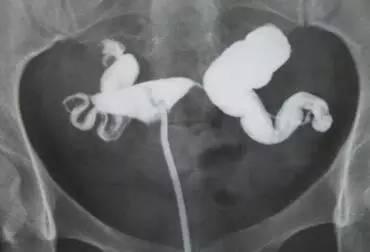

输卵管造影

解说:输卵管堵塞